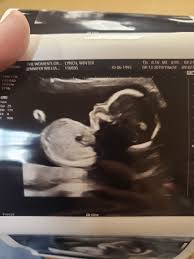

Week 20 Ultrasound What It Would Look Like Parents